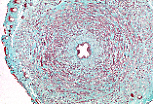

La lumière du canal déférent est étroite et étoilée.

Sa paroi épaisse comporte trois tuniques qui sont, de l'intérieur vers l'extérieur, :

- une muqueuse,

- une musculeuse,

- une adventice.

La musculeuse contient trois couches : une interne longitudinale, une moyenne circulaire et une externe longitudinale.